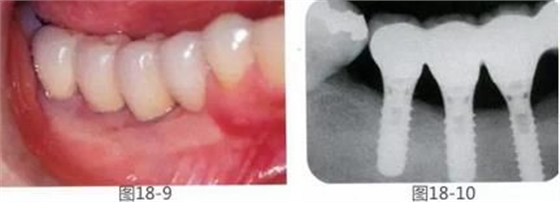

圖18-9,10 GBR修復(fù)后10年。